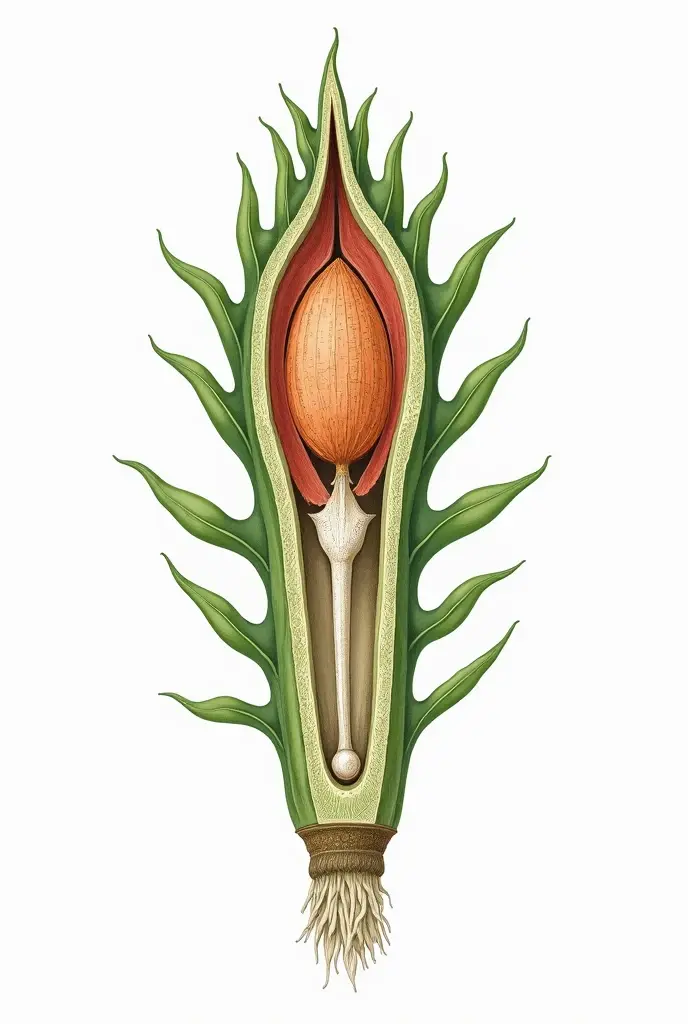

Realice un dibujo de la piel. Coloque las siguientes referencias: Epidermis Fermis Hypodermis Keratinized squamous stratified epithelium Hair Sebaceous gland Sweat gland Pilo erector muscle Connective tissue Blood vessels Nerves Adipocytes

Epidermis Fermis Hypodermis Keratinized squamous stratified epithelium Hair Sebaceous gland Sweat gland Pilo erector muscle Connective tissue Blood vessels Nerves Adipocytes